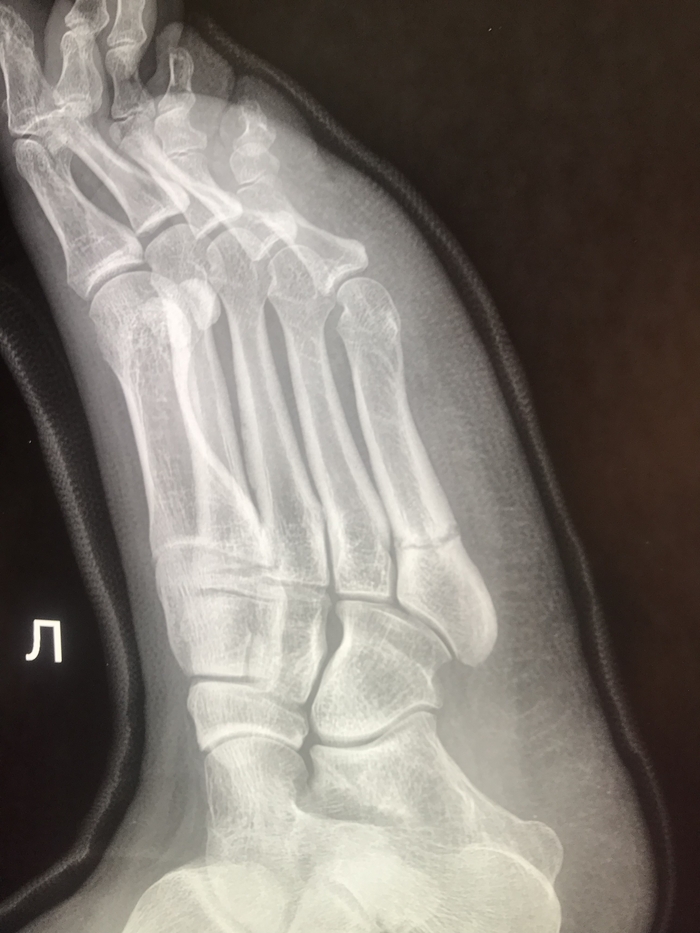

А вот так выглядит перелом пятой плюсневой кости. Пациентка уже с гипсом, сказала что упала с велосипеда.